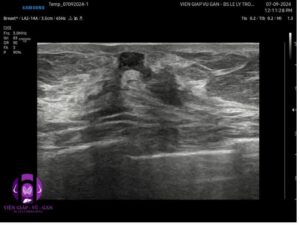

Vú trái:

- Vị trí 1-2g sát núm 2 khối đặc echo kém, hình dạng không xác định, bờ không đều, có chỗ gập góc, giới hạn rõ, trục dọc, không vôi, kích thước từ 5-6mm . Siêu âm doppler tăng sinh mạch máu nhiều, phổ động mạch.

- Vị trí 3g cách núm vú 4 cm có tổn thương tương tự kt# 6mm.

- Kết luận: Đa tổn thương vú trái( BI-RADS 4B)